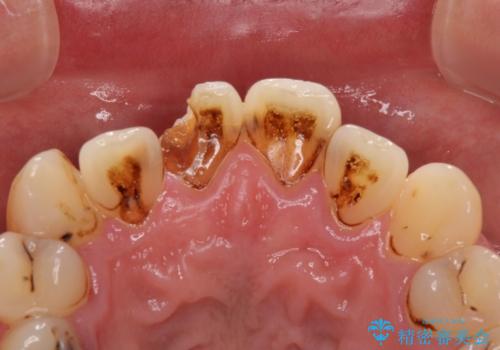

- 前歯や奥歯の虫歯を放置しており、それらの治療を契機に真っ白な歯にしたいとのことで来院された患者様です。

咬み合わせを改善するに当たって、抜歯しなければならない歯や歯列の改善が必要な箇所があったため、矯正治療やインプラント治療から始めていくこととしました。

不自然なくらい真っ白にしたいとのことでしたので、透明感のないフルジルコニアクラウンを用いて補綴することとしました。